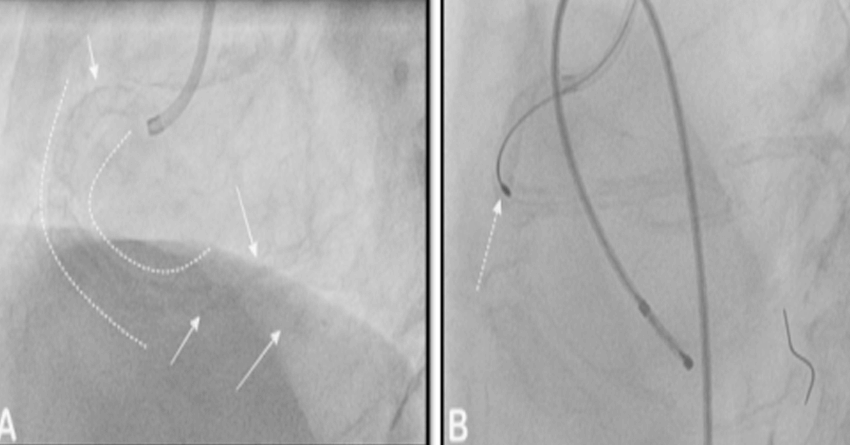

At Yashoda Hospitals, I have addressed many elderly patients who had a heart attack. The oldest patient I treated so far was of 95 years age, he is still surviving without any complications. Let me discuss a case where I did angioplasty for a 75-year-old gentleman who presented with recent onset effort angina on exertion for 15 days. He lived with hypertension and he was a reformed smoker. His coronary angiography revealed calcified right coronary artery [proximal to distal] with critical stenoses of distal two branches namely posterior descending artery [PDA] and postero-lateral branch [PLB]. Left coronary angiography showed mild lesion of the left anterior descending artery and osteal complete occlusion of another left-sided artery, which was blocked for a long time.

Panel A: The curved dashed lines across the entire course of the right coronary artery depicting the presence of the calcium, which posed difficulty in crossing the artery. Panel B: the use of Rotablation for debulking the calcium from the lesion. The Rota burr is seen crossing the vessel under the presence of temporary pacemaker wire as a standby if the patient develops heart blocks leading to low heart rate

To relieve his chest pain I attempted to do the angioplasty of the right coronary artery branches – PDA and PLB as described earlier. But I was facing trouble in passing the smallest size balloon due to extensive calcium in the entire course of the vessel.

Hence the use of the rotablation was advocated which modified the lesion in the artery. Then I could deliver the stent to both the branches and complete the procedure. The left-sided blockages were left on medical management and patient was discharged on the 2nd day after the procedure without any complication with the prescription of regular medications. Patient has completed more than 2 years since the procedure and he is doing very well & leading quality life without any chest pain.